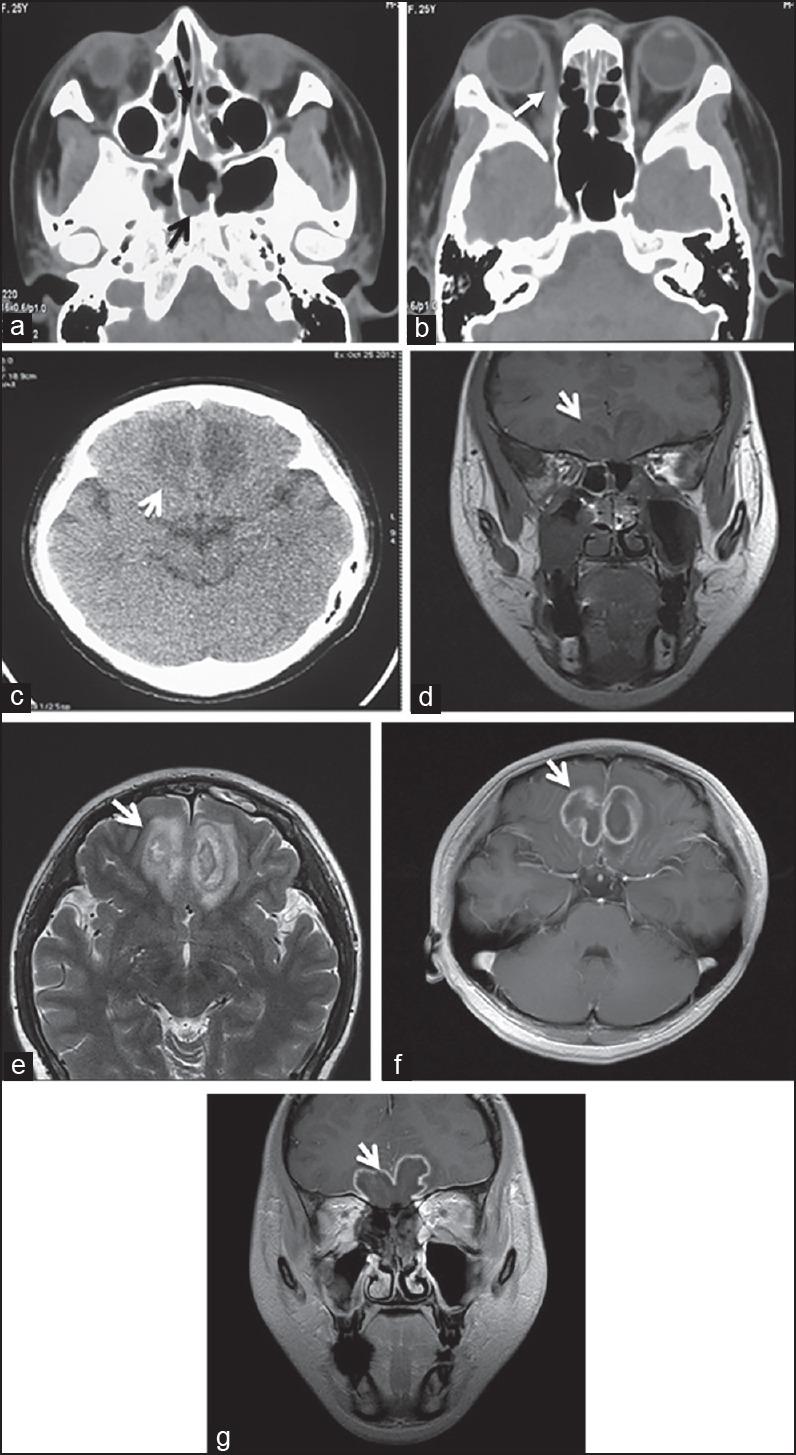

Retrospective Clinical Study of Eighty-One Cases of Intracranial Mucormycosis.

This study has collected the data of 81 cases of intracranial mucormycosis from 28 Chinese hospitals, within 37 years, as well as reviewed the literatures and retrospectively analyzed and summarized this disease's background, clinical classifications, risk factors, pathology, clinical manifestations, diagnosis, treatment, and prognosis.

The 81 IM cases were aged between 15 days (the youngest) and 79 years (oldest), with a mean age of 41.6 years. Among them, 12 cases were <1 year old (the infant group), six cases were within one to 13 years old (the children group), and 63 cases were >14 years old (the adult group ). 45 cases were male and 36 were female, with a male/female ratio of 1.25:1.0. The shortest duration of the disease was three days, and the longest was 248 days.